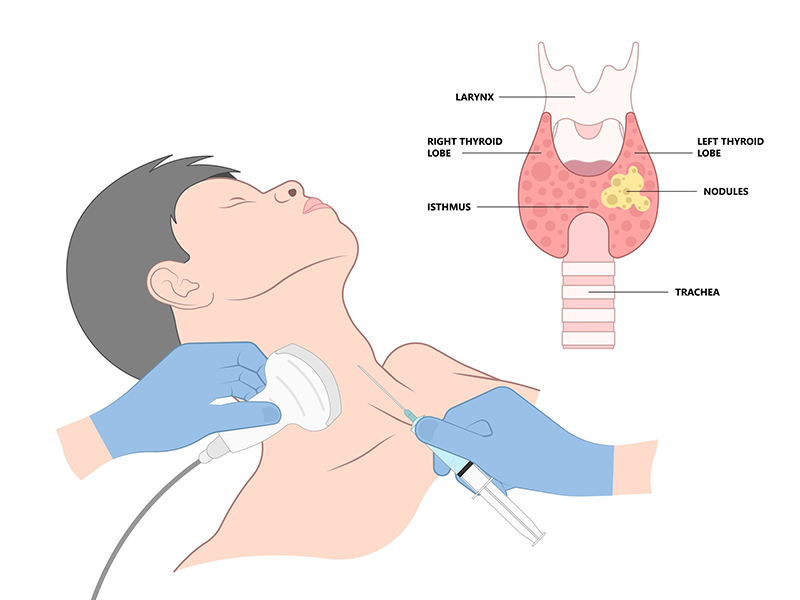

Dedicated small-parts ultrasound for thyroid, breast, scrotal, musculoskeletal, and superficial lesions using high-frequency probes.

Fine-needle aspiration cytology and core biopsy sampling with on-site expertise for accurate tissue diagnosis.

Learn more →M.B.B.S. (KGMC) M.D. (Radio Diagnosis)